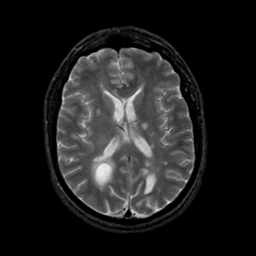

MR Study #21, November 3, 1991 -- Slice #29